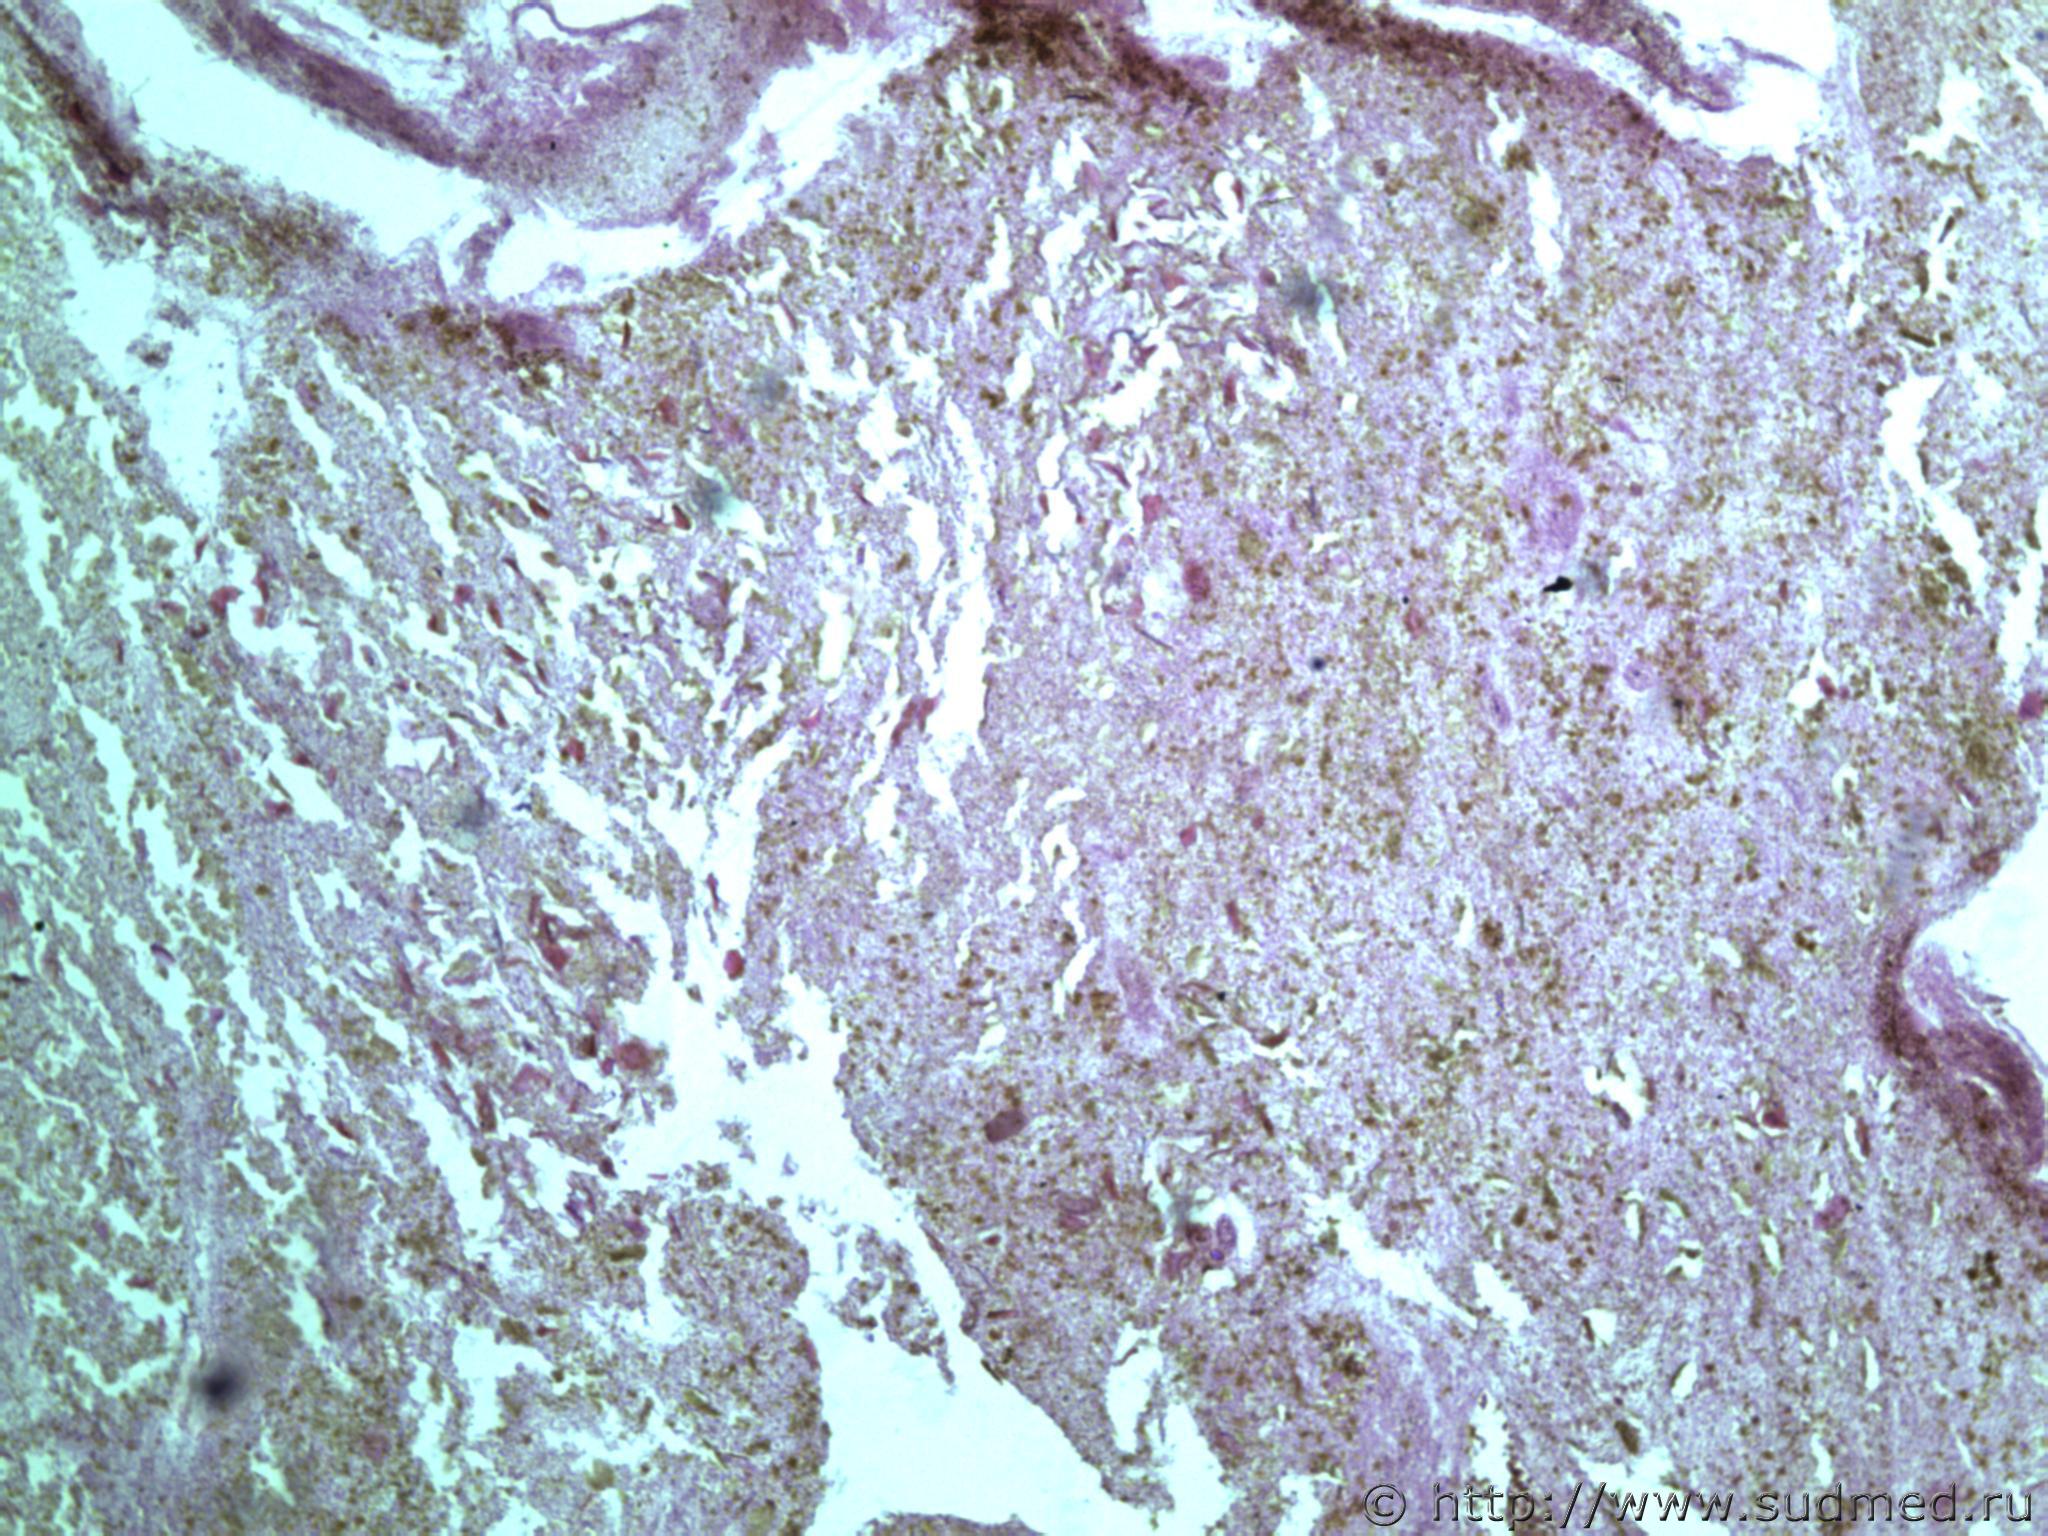

всем здравствуйте. хотела бы знать ваши мнения. провожу экспертизу. препараты как и труп новорожденного гнилые либо в аутолизе страшном. в легком картина такова, что ткань "плотная". просвет различимых альвеол в виде щелей и по всем полям зрения элементы околоплодных вод. одна артерия пуповины спазмирована. остальные сосуды непонятно : просвет их спавшийся но без признаков спазма. они как будто сплющены. да и сама пуповина в виде тонкого тяжа, видно из-за гнилостных изменений. под тмо спинного мозга признаки кровоизлияния, как и в коже с шеи. в коже головы с полнокровием отдельных сосудов. мать утверждает что ребенок после родов не сразу но все же шевелился и кричал. хотя перед этим он выпал у нее из матки на пол, ударившись головой. и со слов матери у него была пена изо рта и он хрипел.

сегодня сфоткаю конечно. но не факт что будут качественные фотки. плавательная проба - "сомнительная".

Судебная медицина - Прикрепленное изображение Судебная медицина - Прикрепленное изображениеСудебная медицина - Прикрепленное изображениеСудебная медицина - Прикрепленное изображениеСудебная медицина - Прикрепленное изображение

Плохо,материал гнилой.

Остановился бы на дышавшем лёгком.

В данном случае лучше вообще уйти от ответа и ограничиться фразой "в виду аутолиза и признаков универсального гниения в ткани лёгкого судить о прижизненном наличии воздуха в альвеолах не представляется возможным"

5 фото в сообщении №4 и 8 фото в сообщении №5 не наводит ли на мысль о дышавшем лёгком ?

Про остальные фото молчу,там или ничего не видно или же есть оптически пустые пузыри,что вероятнее всего,проявления гниения.